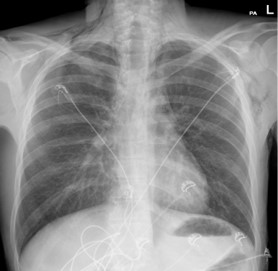

A chest X-ray performed (Figure 1) in the Emergency Department demonstrated significant subcutaneous emphysema. Subsequent computed tomography of the thorax showed extensive pneumomediastinum with a locule of intramural gas possibly reflecting a focal rupture point (Figure 2).

Figure 2: CT Thorax.